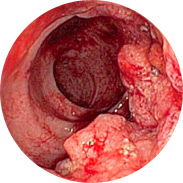

¿qué hace peligrosas las hemorroides en hombres y mujeres?

• Inflamación e infección de la mucosa rectal

• El sangrado puede conducir al desarrollo de anemia

• El aumento de la temperatura corporal, con inflamación severa, puede provocar fiebre

• ¡Y lo peor es el cáncer rectal!